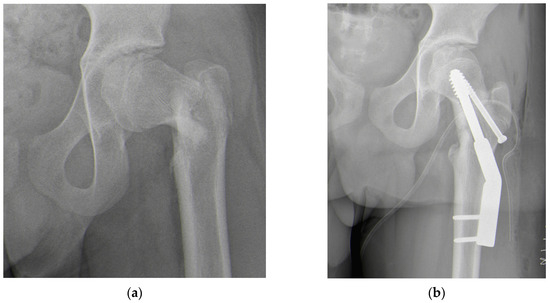

2. Case Presentation

2.4. Results